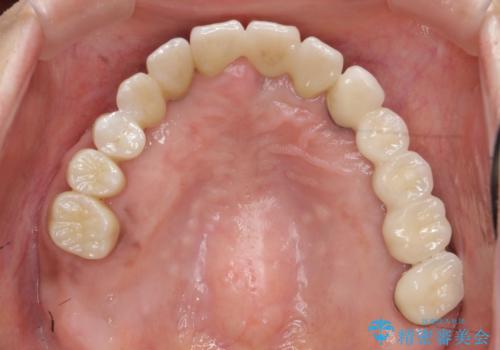

痛くて噛めない インプラントで全て治療したい

- 痛くて噛めない、これまでだましだまし治療をしてきたがこれを機にすべてきっちりと治したい、口の中の悩みを解決したいと来院されました。

抜歯や歯周病治療、欠損補綴を含め、全顎的な治療を計画・提案します。

口腔内に歯の破折や歯周病、虫歯、欠損など複数の問題が存在する場合局所的に問題を解決していくのではなく全顎的な治療を行っていくことで長期的な予後を見込むことができます。